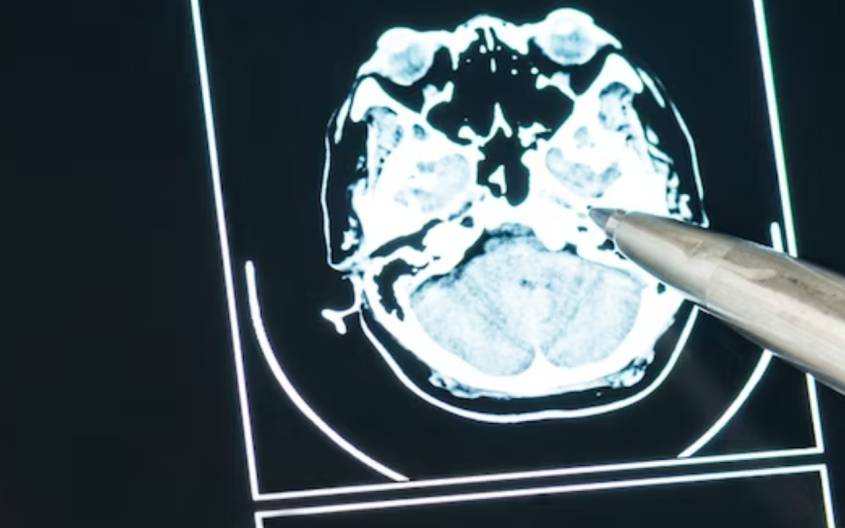

Инсульт, как последствие гипертонии — врачи предостерегают

В Камчатском центре общественного здоровья рассказали о симптомах, сигнализирующих об инсульте, заметив которые, следует вызвать скорую помощь:

головокружение, потеря равновесия и координации движения; проблемы с речью (человек не может назвать свое имя); онемение, слабость или паралич одной стороны тела; потемнение в глазах, двоение предметов или их размытие; внезапная сильная головная боль.